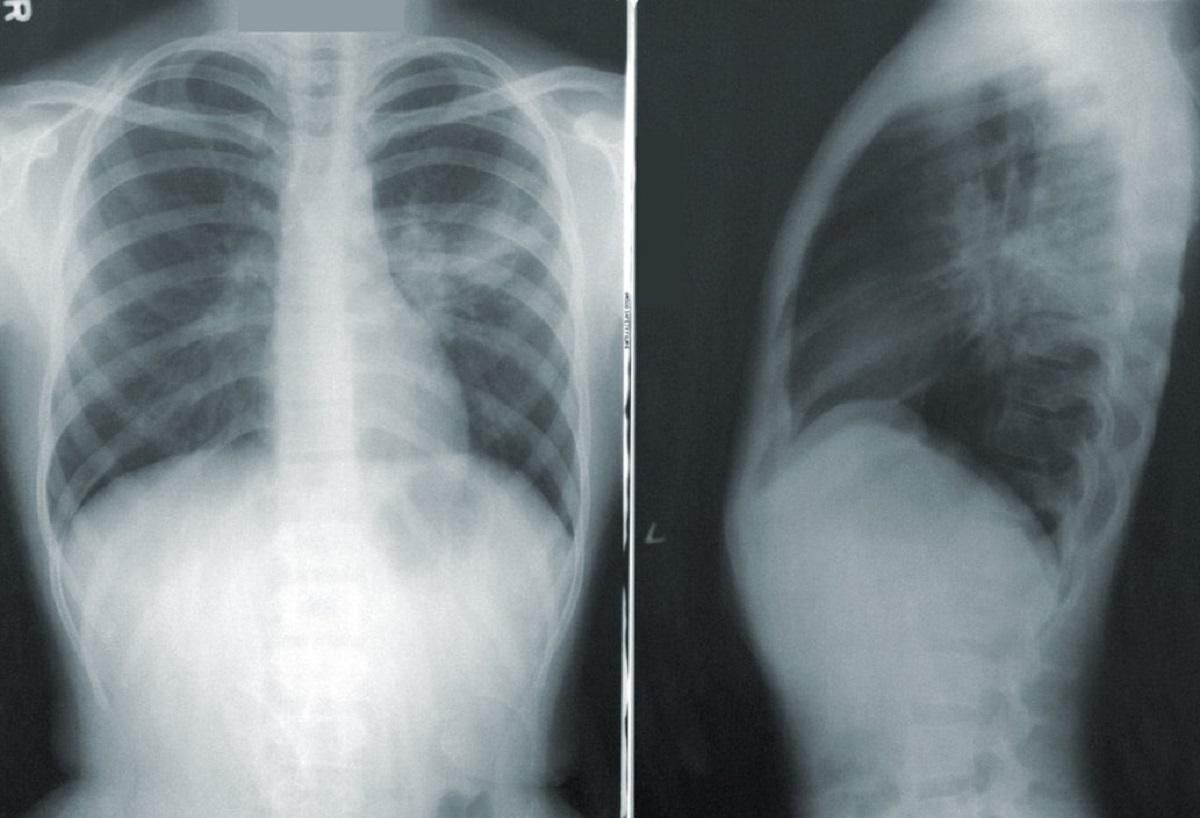

Також КТ призначають, зважаючи на важкий стан пацієнта (навіть якщо ПЛР-тест показує негативний результат). У МОЗ пояснили, як отримати та скористатись направленням на безкоштовну комп’ютерну томографію.

Рішення про видання чи не видання направлення повинен вирішувати лікар, опираючись на загальний стан пацієнта, наявність дихальної недостатності, показник сатурації (насиченості крові киснем) та температуру тіла.